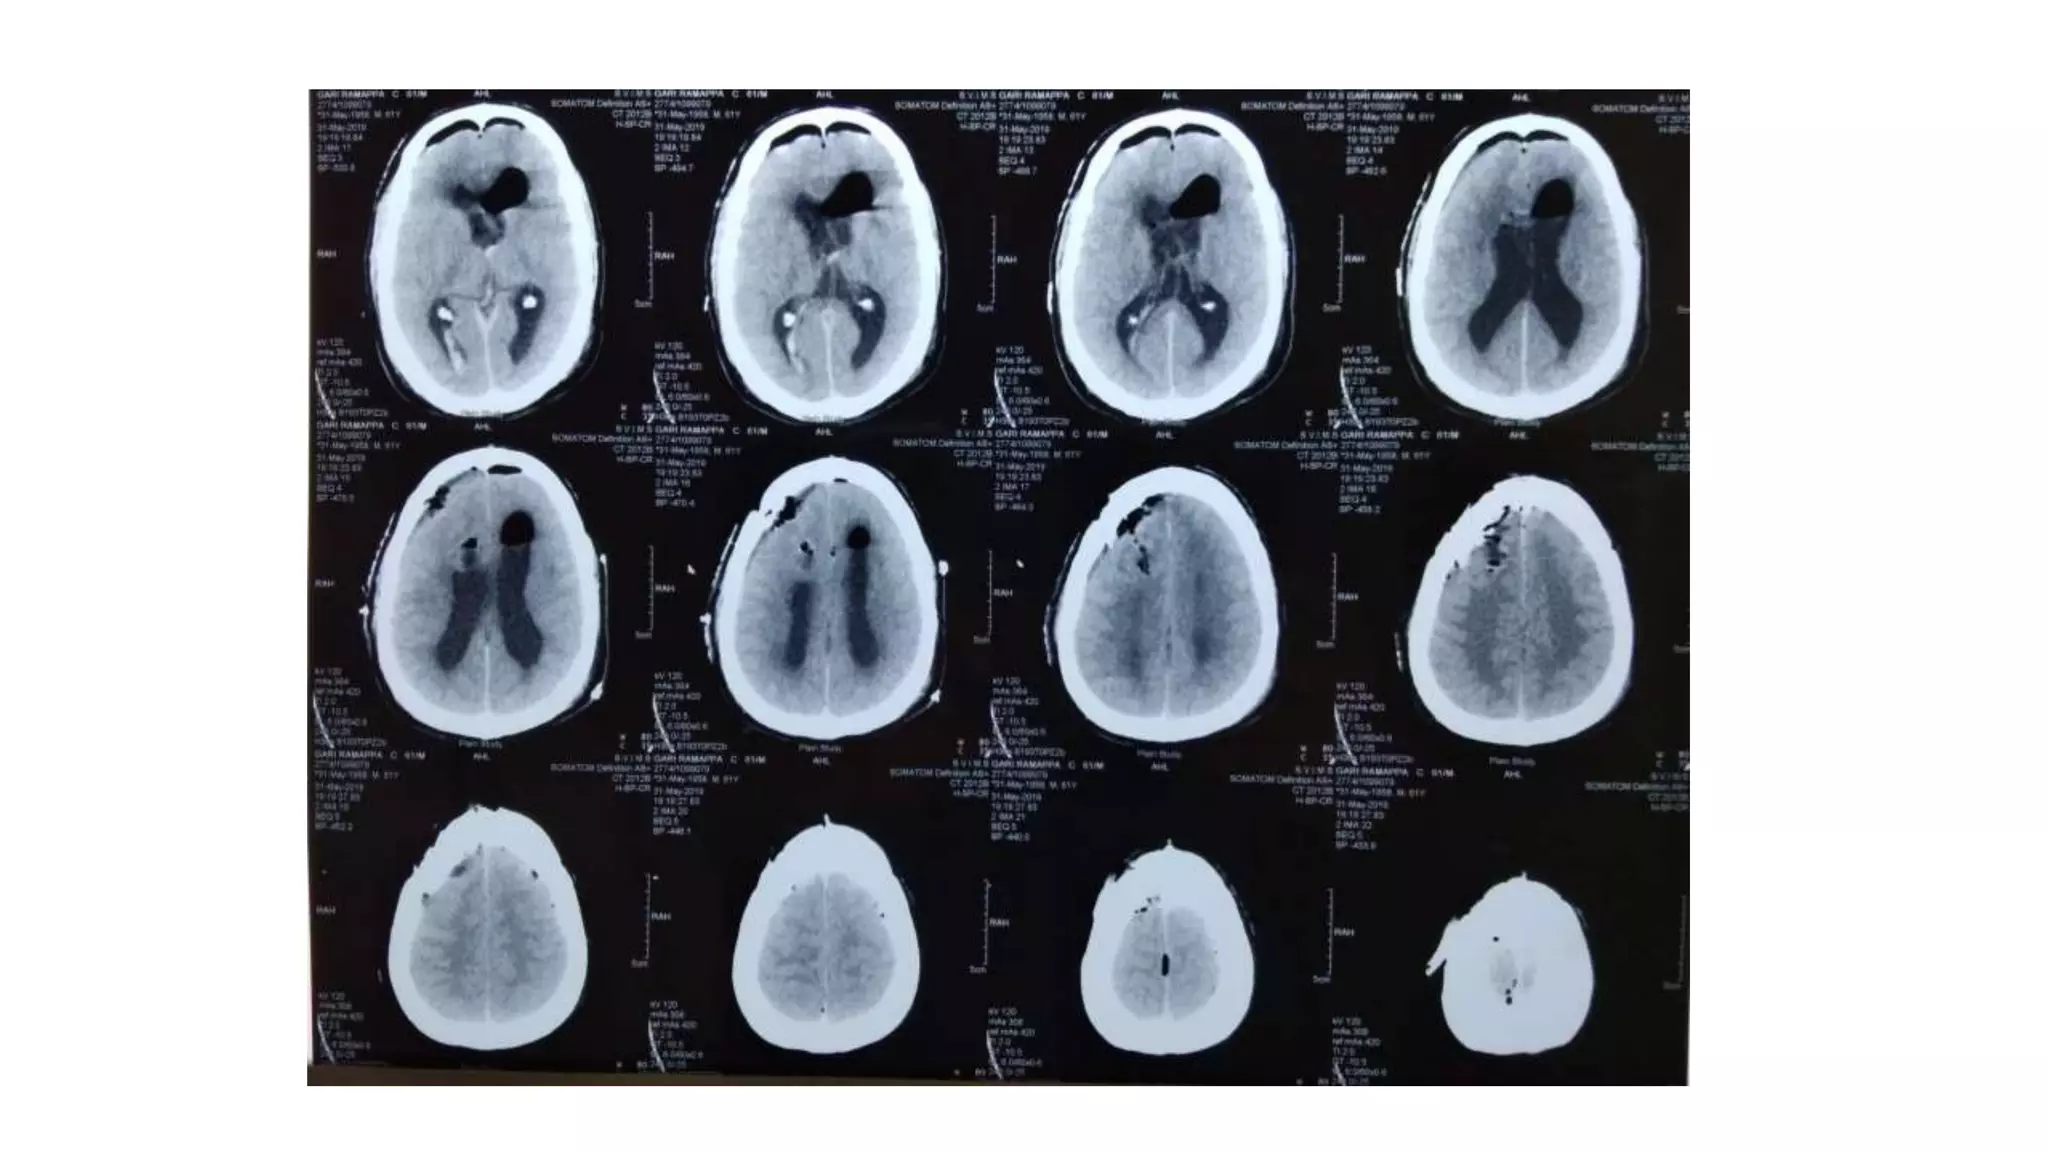

Trends in our Institute:

• 36 patients were studied retrospectively

• 19 patients underwent trans cortical approach

• 13 underwent trans callosal approach

• 3endoscopic trans cortical and

• 1 endoscopic trans callosal

• Common complications faced were Hydrocephalus,CSF leaks and

meningitis all in trans cortical approach

• No complications were noted in endoscopic approach

• No recurrence was noted in either of the procedures